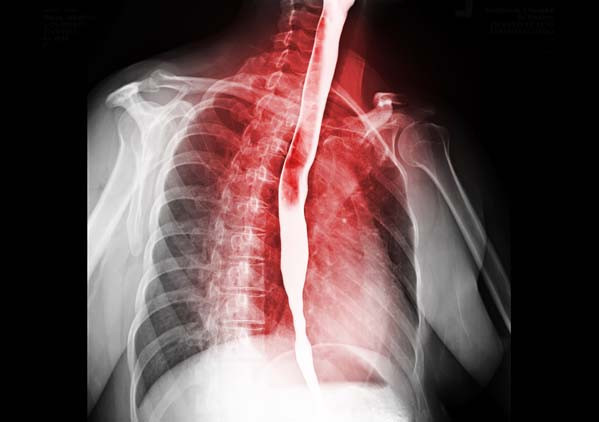

Tüm bu acıların ardından altı ay sonra doktor inanılmaz bir haber verdi: Tümör o kadar küçülmüştü ki lenf düğümlerinde neredeyse ölçülemez hale gelmişti. Yemek borusundaki tümör ise bir elma boyutundan ceviz boyutuna gerilemişti.

Bu başarı, Andrew’un artık ameliyat edilebileceği anlamına geliyordu; ‘özofajektomi’ yapılacaktı yani sağ akciğeri söndürülecek ve yemek borusunun yaklaşık 15 santimetrelik kısmı kesilip atılacaktı.